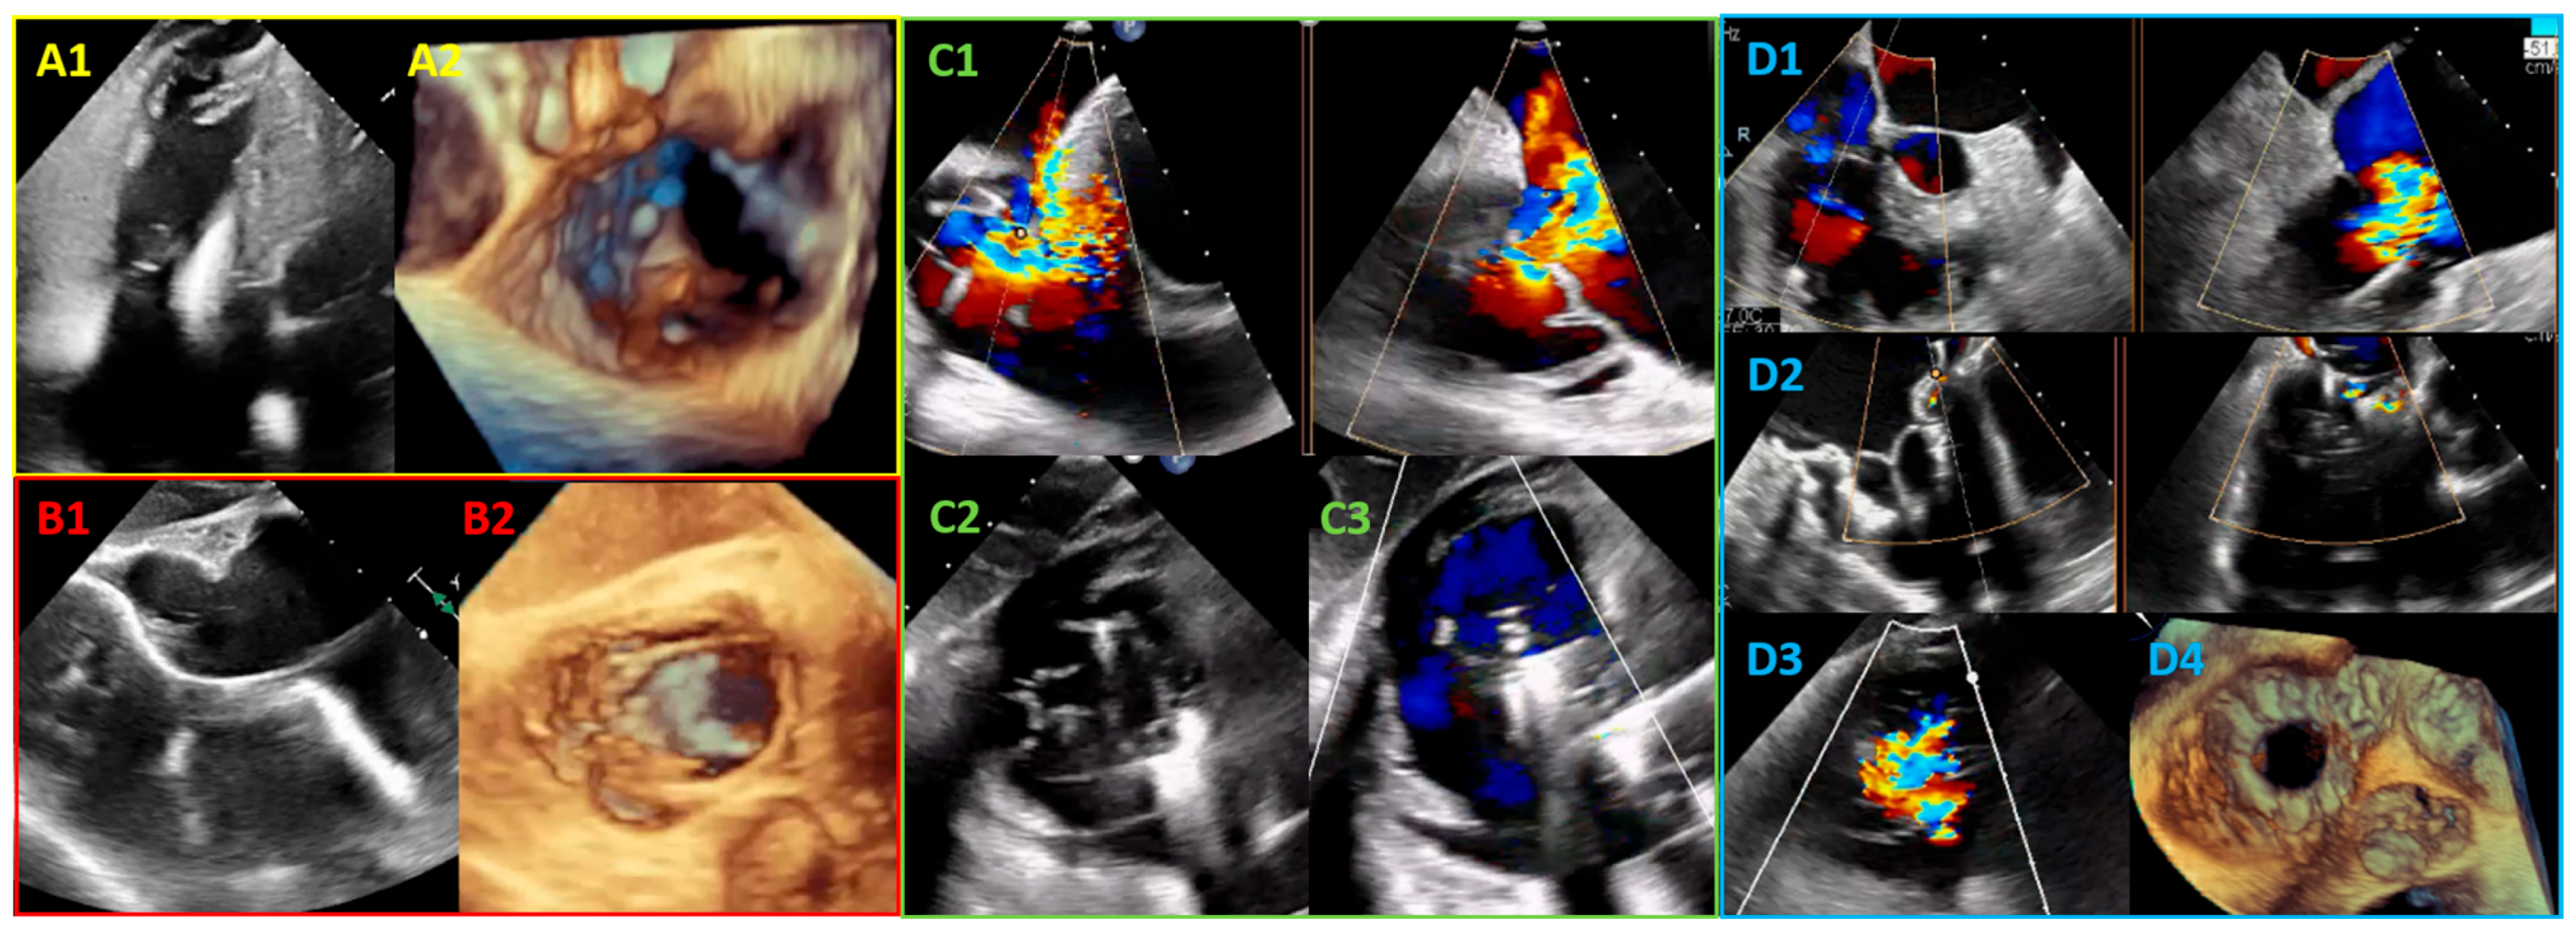

3.1. Transcatheter Edge-to-Edge Repair